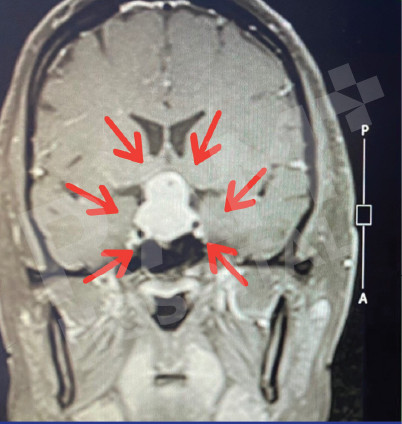

磁共振成像(MRI)可清晰、细致地显示垂体的异常病变,精准定位垂体腺瘤的位置;结合静脉造影增强检查,还能明确腺瘤的具体位置与病变性质,同时清晰呈现脑部周边组织及鼻窦的情况。这一项检查结果可为制定诊疗方案、随访评估垂体腺瘤的治疗效果,乃至规划手术方案提供明确、可靠的依据。